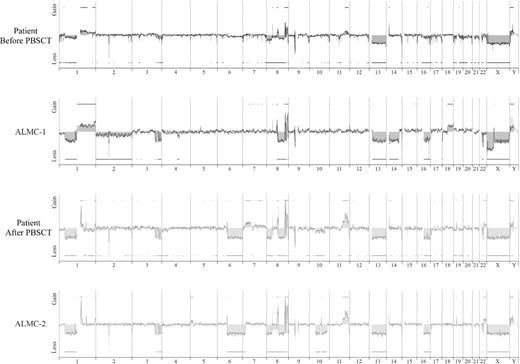

We next used array CGH, a methodology that permits a much higher resolution map of the 4 genomes than that achieved by conventional methods (Figure 4), to test the genetic relationship between the cell lines and the primary patient cells. This analysis permits 2 major conclusions. First, the data clearly demonstrate the overall similarity between the cell lines and the patient primary cells. Second, a number of genetic changes were acquired during the course of disease progression, including regional chromosomal gains in 1q, 11q, and 22q, and losses in 6q, 8p, 10p, and 10q, several of which have been associated with poor prognosis myeloma (reviewed by Tonon30 ). Of interest, 6q deletion is frequently observed in Waldenstrom macroglobulinemia and is associated with features of adverse prognosis.31

Genome-wide high resolution aCGH. Chromosomal copy number alterations across the pre-PBSCT, ALMC-1, post-PBSCT, and ALMC-2 cells are plotted for each probe evenly aligned along the x-axis in chromosomal order.

Although it is beyond the scope of this report to present a detailed analysis of all gains and losses, Figure 5 presents a more detailed view of chromosomes 1, 3, 8, and 22. Chromosome 1q21 is amplified only in the primary patient cells post-PBSCT and the ALMC-2 line. This region has a number of interesting genes that have been shown to play a role in other cancers, including the transcription factor, Arnt32 ; the Bcl2 family member, Mcl133 ; the micro RNA, MIRN55434 ; FLG2, a member of a family of genes whose products interact with intermediate filaments35,36 ; and the DNA-binding histone protein, HIST2H2AB.37 Several regions on chromosome 3 have undergone losses in all 4 samples tested and include ABCC5, a multidrug resistance gene,38 and ATP13A5, a lipid-transporting p-type ATPase.39 The transcription factor, TRMT12 (chromosome 8), has been shown to be amplified in breast carcinoma40 and is amplified in both primary patient samples and both cell lines (Figure 5). Finally, losses were also observed on chromosome 22 in all 4 samples. One of these regions includes the IGL locus and probably reflects genomic DNA lost on chromosome 22 during VJ rearrangement. Consistent with λLC expression, there is a biallelic loss of the κLC locus on chromosome 2p12 in all 4 samples studied (Figure 4). The second region of chromosome 22 loss highlighted involves the NF-2 gene, a known tumor suppressor gene.41,42 Collectively, these data demonstrate how closely the in vitro passaged cell lines resemble the primary patient cells. This analysis also demonstrates how the cell line established from the diagnostic marrow similarly evolved, albeit in vitro, in a way that largely mirrored in vivo evolution of the primary tumor.

Shared and emerging chromosome copy number abnormalities. Whole chromosome plots of chromosomes 1, 3, 8, and 22 are shown for the 4 samples. Arrows point out examples of gains or losses that appear uniformly across all 4 samples (chromosomes 3, 8, and 22), or are acquired during the course of disease progression (chromosome 1). The predicted number of gene copies is indicated on the top of each panel.